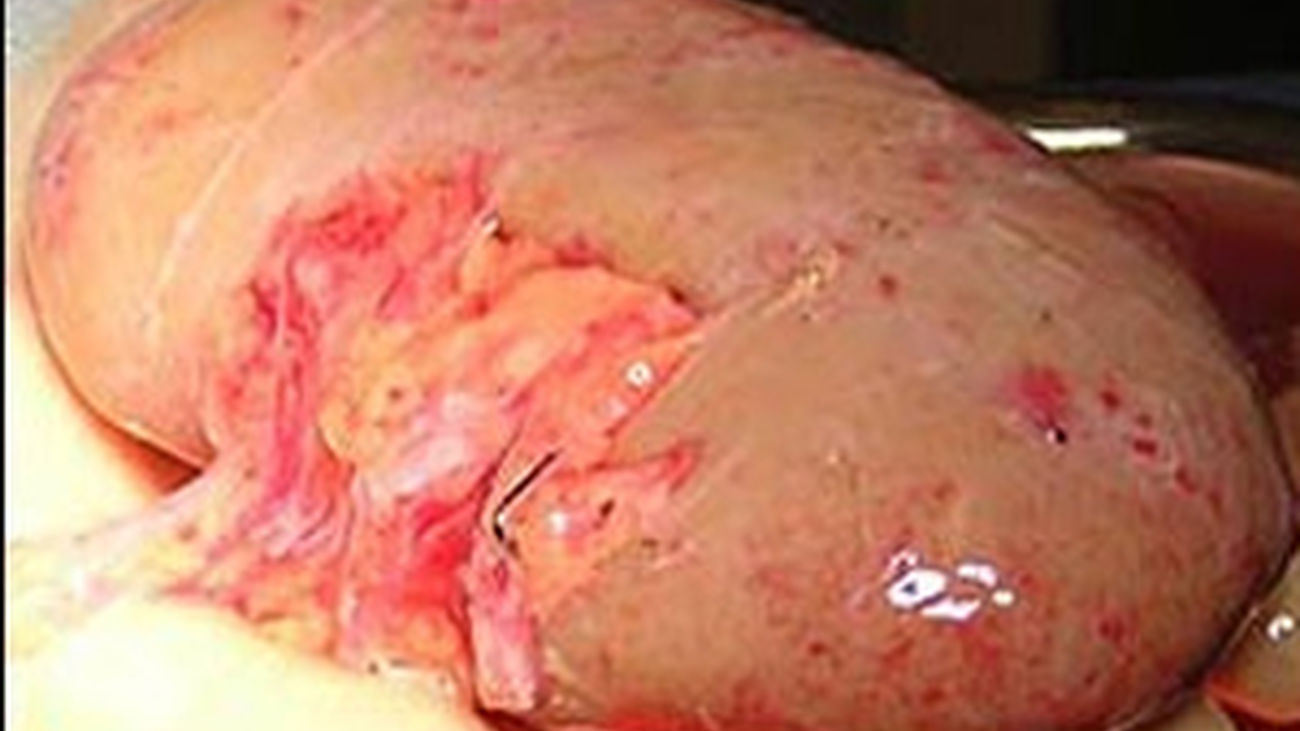

rinon_transplante

rinon_transplante |archivo